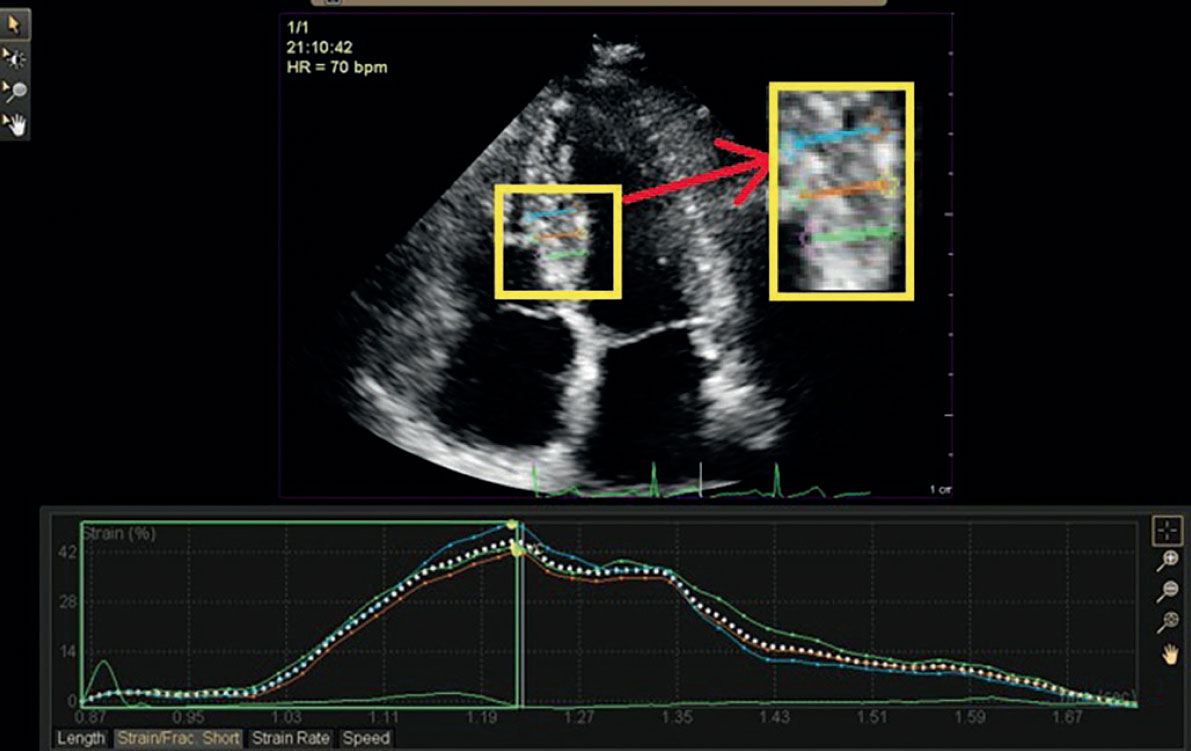

Figure 2. Regional radial strain analysis of a study participant with stable coronary artery disease showing 42% strain of the mid inferoseptal segment.